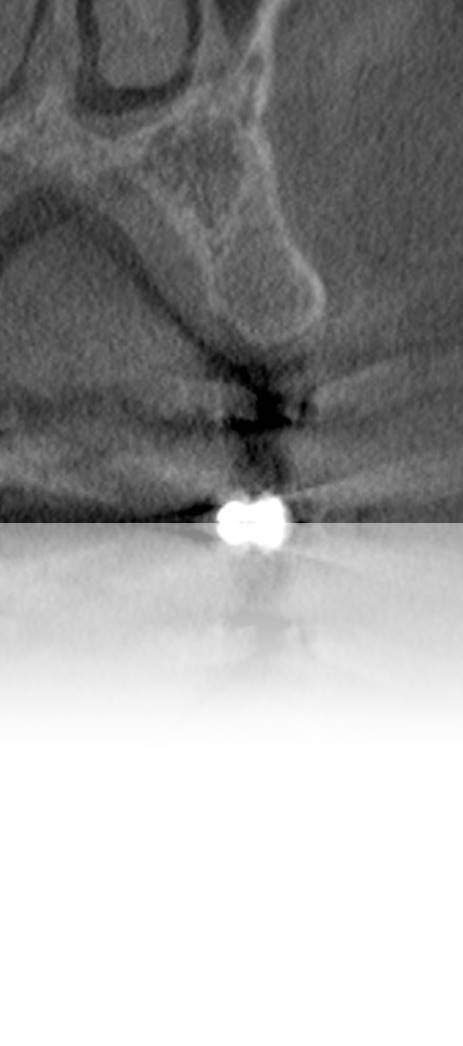

Figure 2. Preoperative radiograph suggests a straightforward implant placement case, with ample space and sufficient bone for positioning the implant.

Figure 2